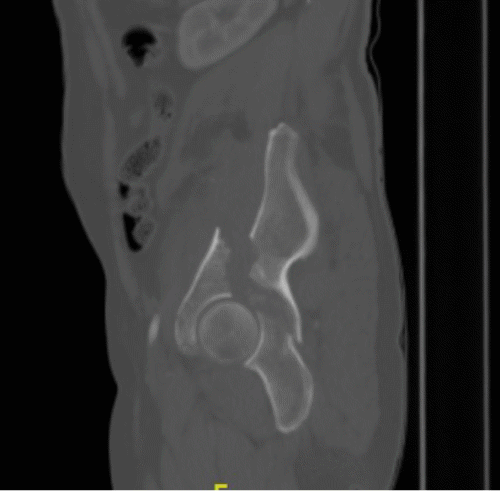

The patient's condition stabilized, and the pain was controlled with analgesia. CT showed no brain injury, but there were multiple left-sided comminuted rib fractures with displacement along the posterior and lateral aspects. In addition, it revealed the presence of hydropneumothorax; lung contusion with thoracic wall subcutaneous emphysema; right-sided mild pneumothorax; undisplaced fracture of the sternal body; herniation of the stomach into the pericardial cavity (Figure 1); no intraabdominal fluid or air and no solid organs injury; fracture of the transverse processes of the L3/L4 and L5 vertebrae; fractures of the left glenoid bone and left pelvic bone; multiple comminuted displaced fractures involving the iliac, acetabular, and pubic bones, with the displacement of the iliac bone fractures; right inferior pubic ramus nondisplaced fractures; and fracture of the left sacral alar and proximal left sacral segments (Figure 2).

Figure 1. CT of Herniated Stomach into Pericardial Space. A) Scout, (B) Axial, (C) Sagittal, and (D) Coronal Views. Published with Permission

C) Sagittal View

Figure 2. Bone CT of Pelvic Fracture. A) Axial, B) Sagittal, and C and D) Coronal Views. Published with Permission

B) Sagittal View